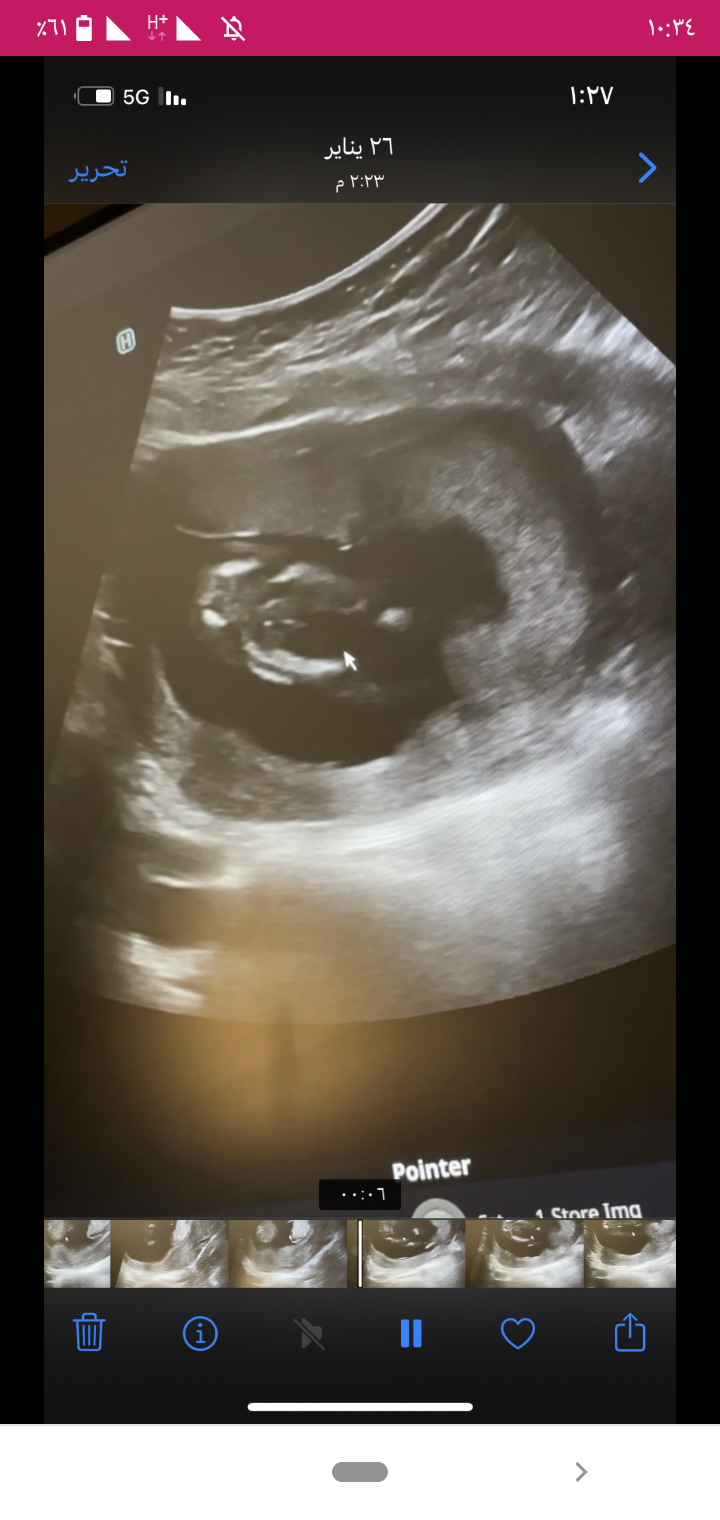

بدور مبروك البنوته ربنا بجيبها بالسلامه ومتقلقيش من جوزك هو معزور مش قصه ولد او بنت بس عشان هو عرف من الاول ولد حصلت معايا ف بنتى الرابعه ودلوقتي هى احب بنت لابوها بس فى حاجه أنا لاحظتها فى الصوره عندك لو دققتى هى فعلا بنت من الاول الدكتوره ال قالت ولد هى ال غلط او مش فاهمه شوفى الفيديو ال انتى مصوراه فى لقطات واضحه جدا أنها بنت انا شوفتها ف الصوره ال انتى حاطتها شوفى كده الصور ال تحت دى اعملى زوم ودققى فيها

شوفى الصوره ال فوق رسمه القلب والصوره ال جنبها واضحه أنها بنت

انا سويت مرتين عشان اتأكد كلهم قالو بنت اكيييد وزوجي طبيب برضو شاف قال بنت